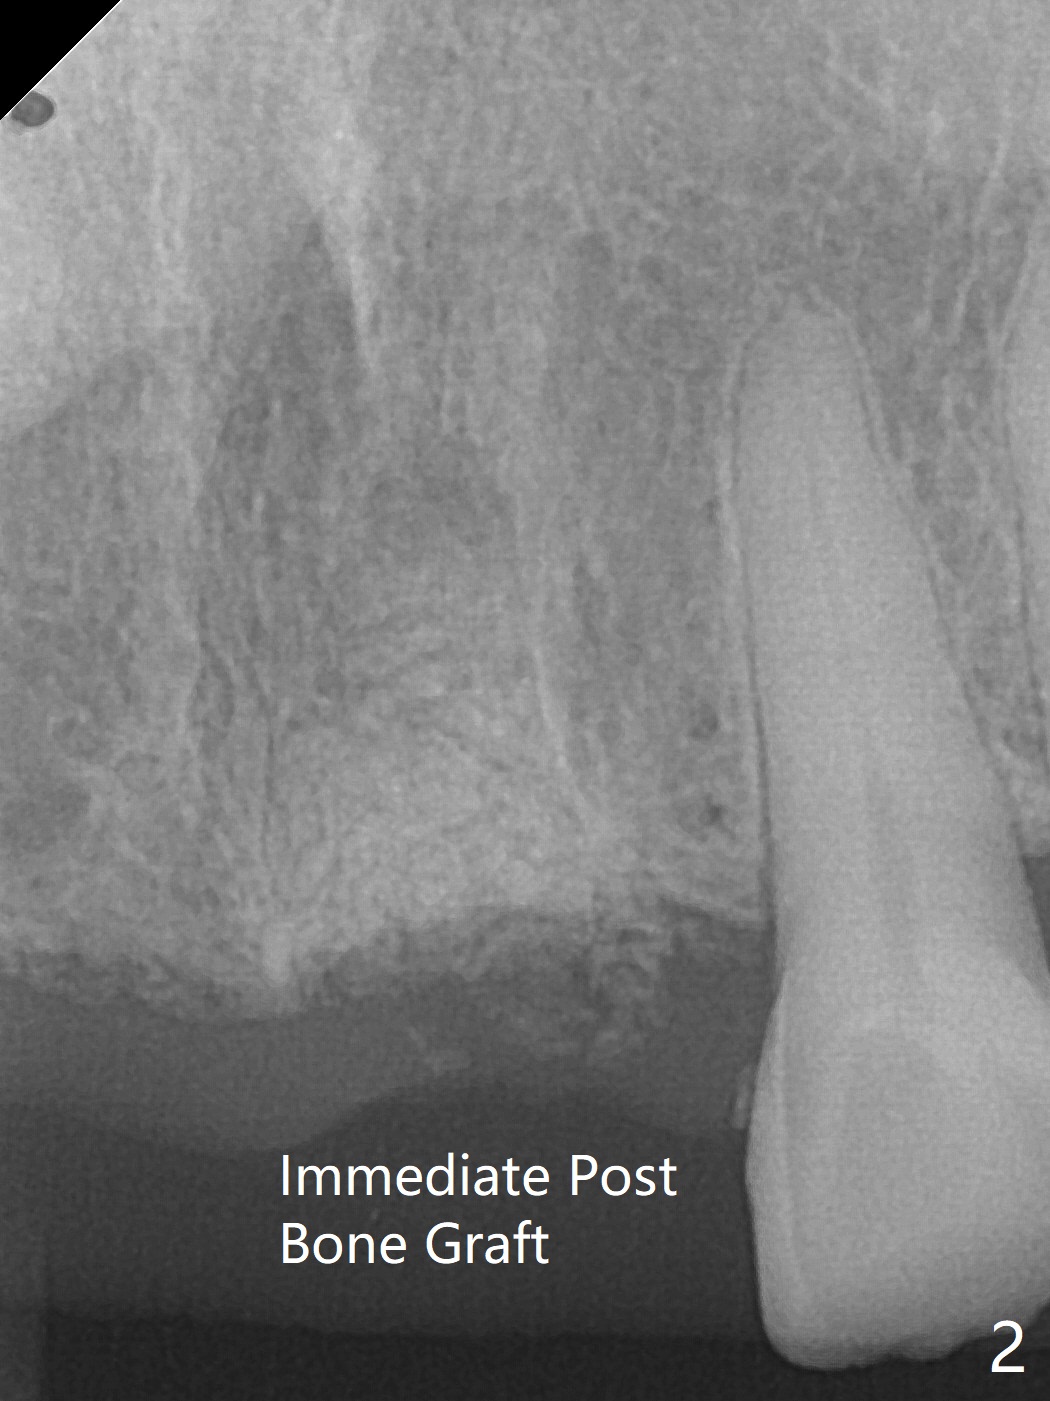

A 63-year-old woman with coronary artery disease and hypertension (taking 100 mg Aspirin daily with bleeding tendency) presents to office with subgingival fracture of the tooth #9 (Fig.1). After packing sticky bone into the extraction socket with a condenser (Fig.2), two pieces of PRF membranes are placed, followed by loose suturing with 4/0 Chromic gut suture (Fig.3). In fact the paper-thin buccal plate becomes bulging post bone graft condensation (*).